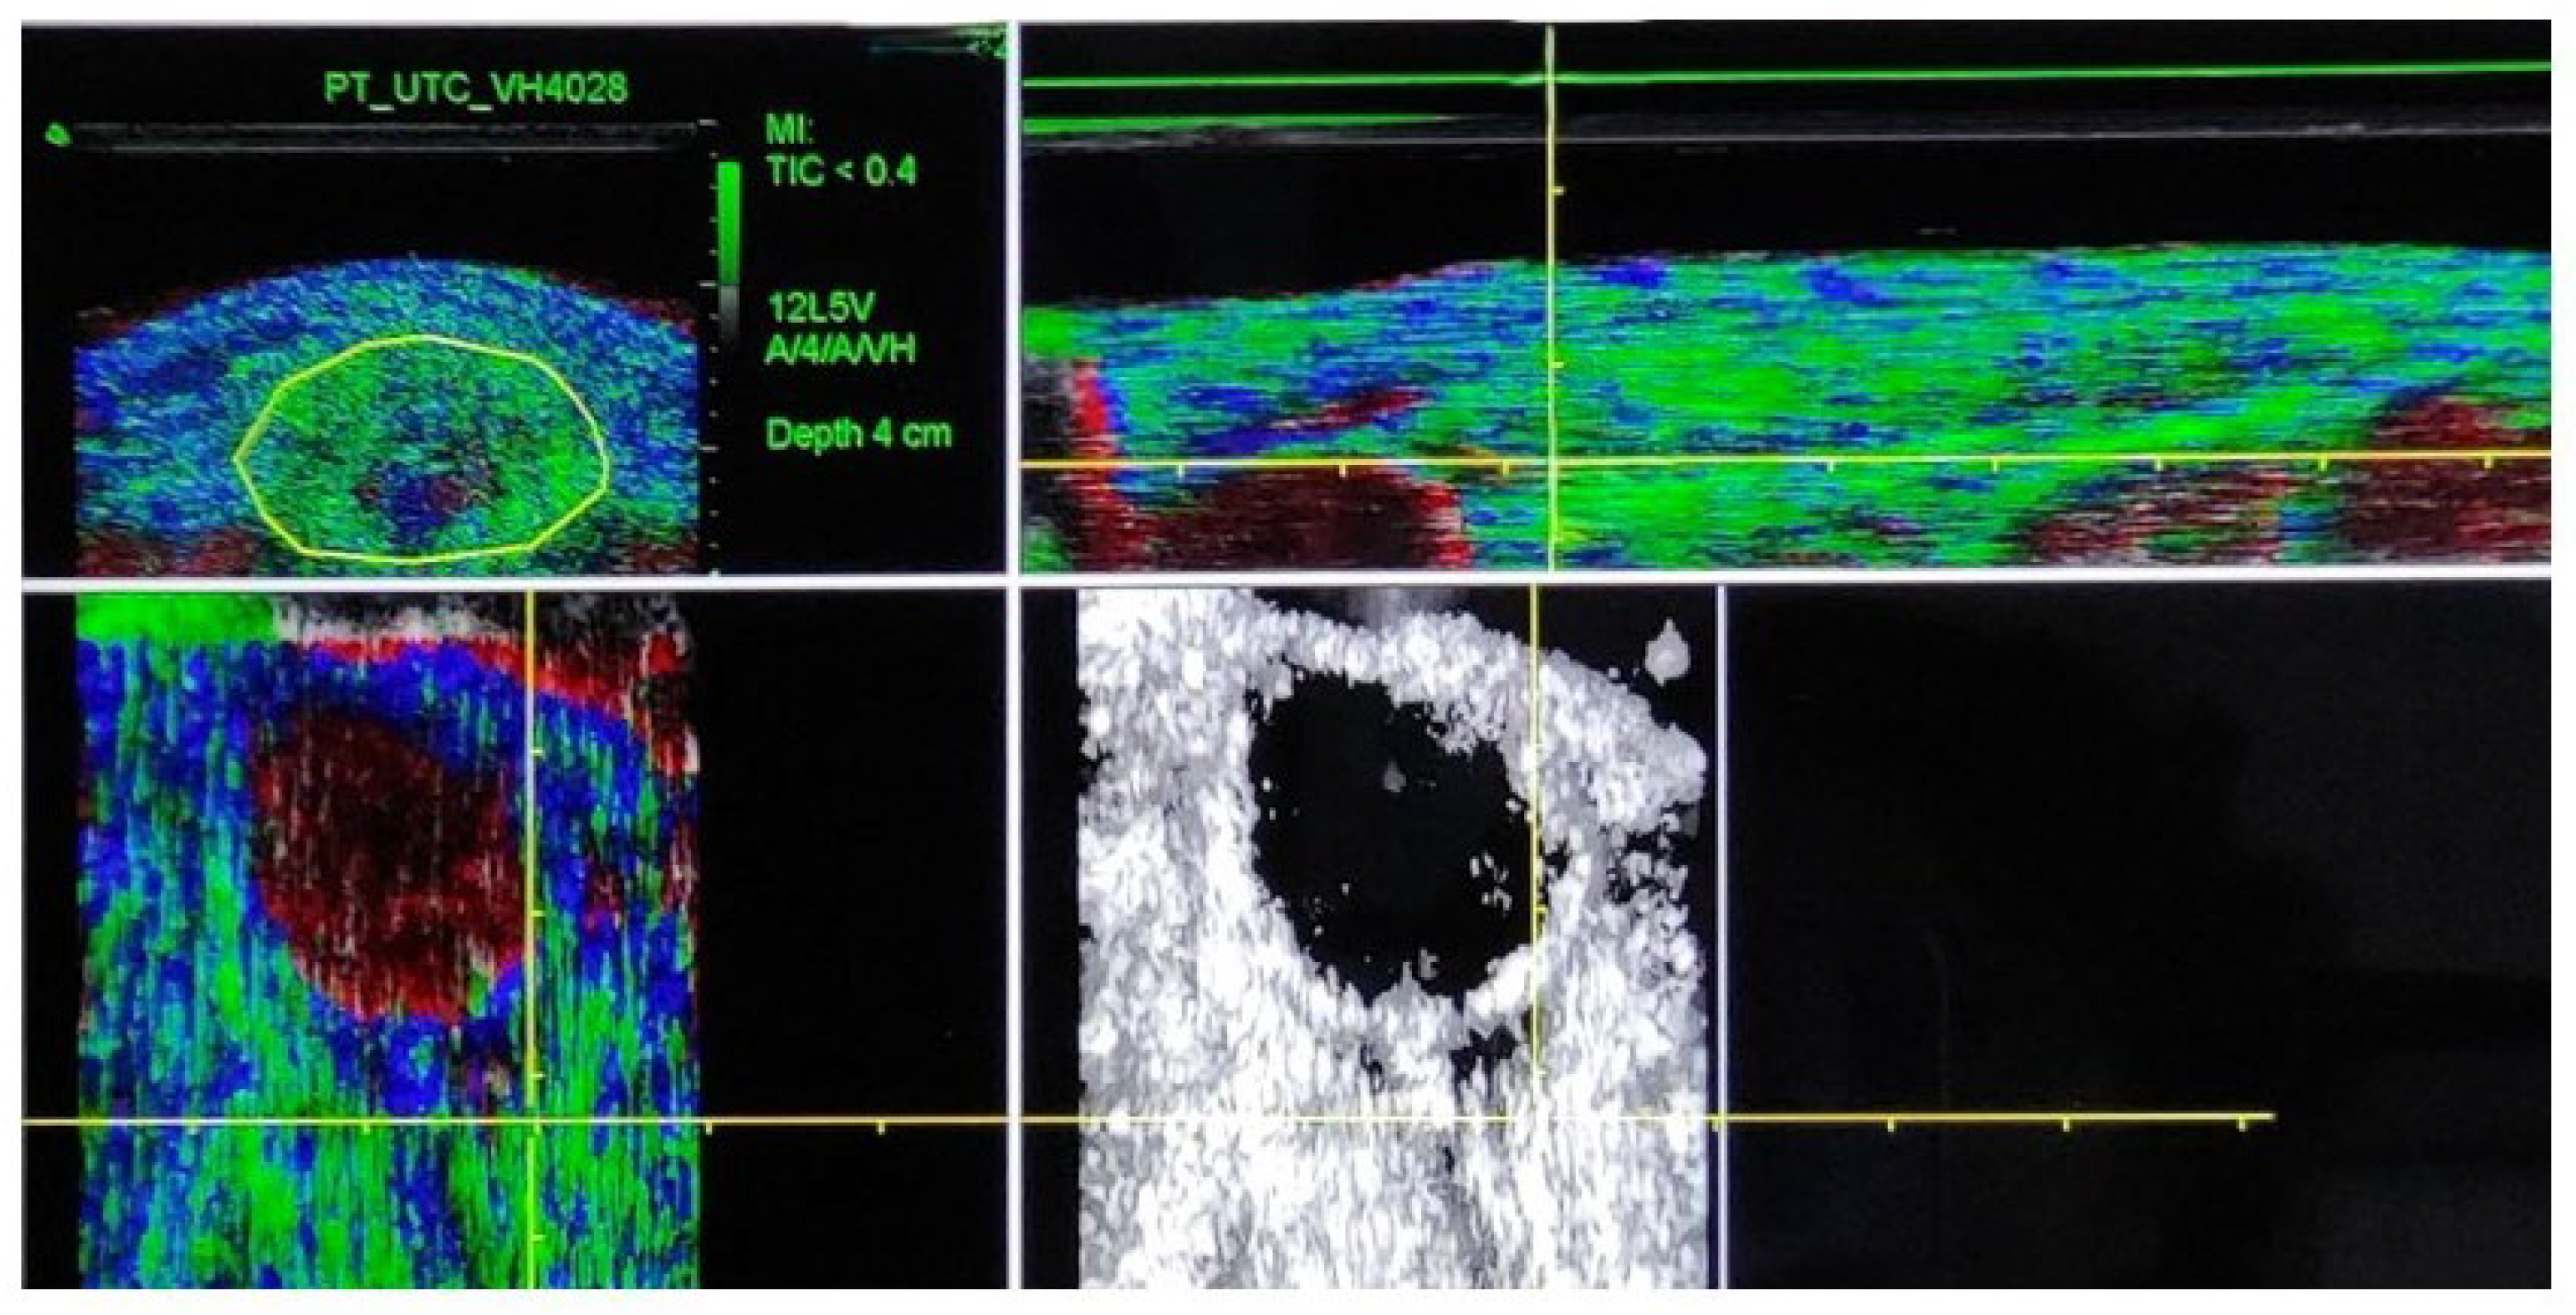

Bilateral UTC scans of the patellar tendon were conducted at the following three times during one season: at the start of the season (baseline), four months, and eight months after the baseline scan. All tests were performed by a single, experienced tester (SOC) to minimize potential inter-tester bias [27]. UTC scans were performed using B-mode ultrasound with a linear transducer of 7–10 MHz (SmartProbe 10L5; Terason 2000, Teratech, Burlington, MA, USA). An ultrasound probe (SmartProbe 12L5-V, Terason 2000+; Teratech) was fixed to a tracking device (UTC Tracker, UTC Imaging) that automatically moved the transducer on the perpendicular axis of the tendon, recording cross-sectional images at 0.2 mm intervals [27]. The consistency of the intensity and distribution of gray images was calculated over a 4.8 mm window, using UTC algorithms to define the echo-patterns. Four echo-types were identified based on the consistency of gray images, with echo-types I and II representing the most continuous/aligned tendon structure, and echo-types III and IV representing the more unstructured/disorganized tendon fibers. Echo-types are reported as a percentage of the total region of interest (ROI) volume. A window size of 17 was used for imaging analysis. The ROI was located around the tendon in the transverse view, with contours drawn at the proximal tendon (20% of tendon length) and the mid-tendon (50% of tendon length) [16,24]. Total tendon length was measured from the inferior angle of the patella to the most proximal part of the tibial tuberosity [16,21,24]. Tendon contours were marked by an experienced investigator (SB) to increase the reliability of UTC outcomes [28]. Echo-types were quantified automatically by the UTC software (UTC 2010) [21] (Figure 1).

Figure 1. Ultrasound tissue characterization of the patellar tendon. Echo type classification; green = echo type I, blue= echo type II, red = echo type III and black = echo type IV: Right upper imagen (area of interest) = transversal view; left upper image = longitudinal view; right lower image = axial view; left lower image = axial view without UTC software classification.